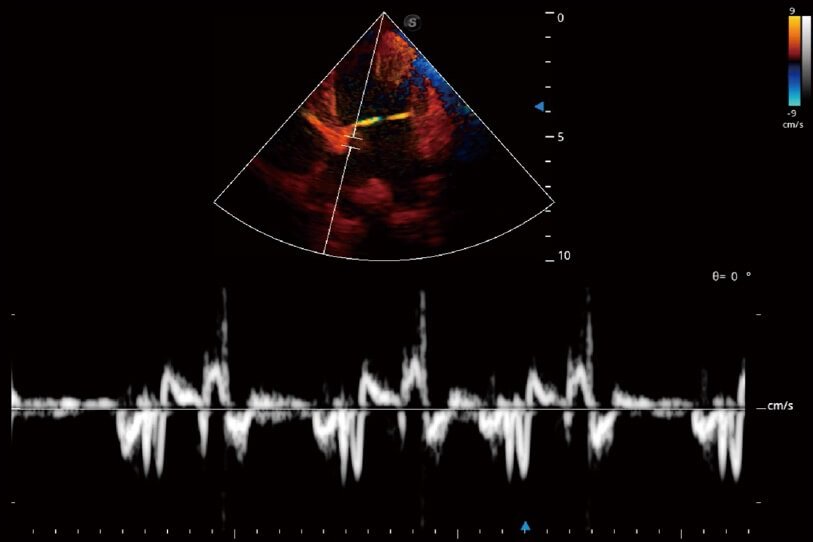

通過(guò)創(chuàng)新的 Matrix E自適應(yīng)濾波器和超長(zhǎng)時(shí)間域算法,極大提升超低速微細(xì)血流的檢出能力,同時(shí)更精準(zhǔn)地濾除軟組織和噪聲信號(hào),為獸用醫(yī)生提供以往無(wú)法通過(guò)常規(guī)血流獲得的疾病診斷信息。

實(shí)時(shí)用顏色表示心肌組織運(yùn)動(dòng),觀察和定量組織的運(yùn)動(dòng)情況,對(duì)快速檢測(cè)與評(píng)估心肌的灌注和活性、電傳導(dǎo)及心肌收縮和舒張功能等均能提供重要的診斷信息。